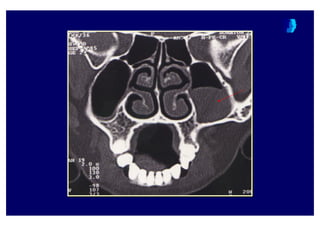

Water’s grafisiWaterWater’’ss grafisigrafisi

Coronal BTCoronalCoronal BTBT

BT ne zaman istenmelidir ?BT ne zaman istenmelidir ?BT ne zaman istenmelidir ?

• Yo4un bir tedaviye cevap al namad 4 taktirde

KBB uzman taraf ndan

• Komplikasyon riski ta( yan olgularda

• Pre-operative de4erlendirme